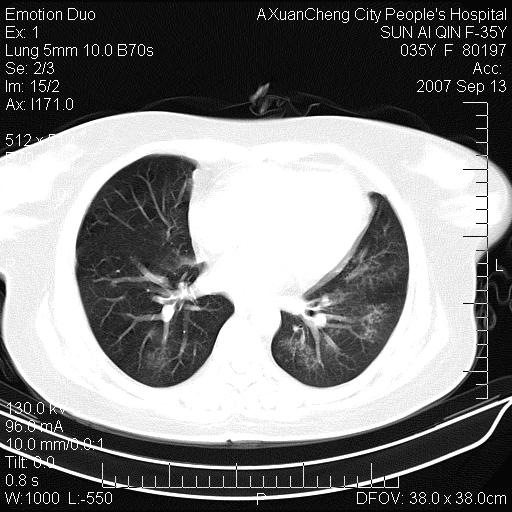

以下是引用天南地北在2007-9-13 13:43:00的发言:[br]考虑双肺、肺门侵润

以下是引用ydx_74在2007-9-13 15:42:00的发言:[br]仅看片,考虑右上肺癌并双肺转移,结合病史,考虑肺门、肺内淋巴侵润

以下是引用同在2007-9-13 15:08:00的发言:[br]支持肺门及双肺侵润.